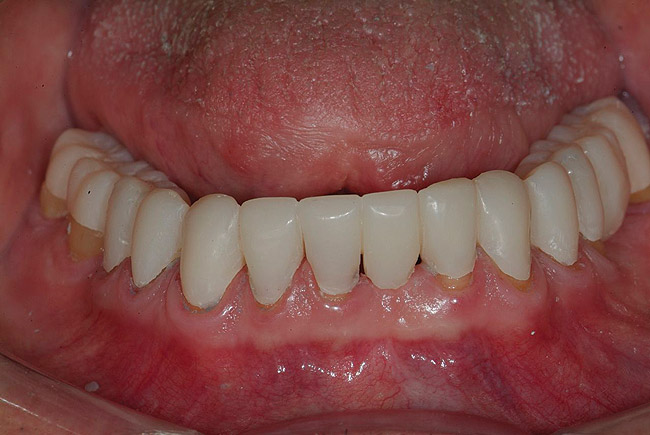

Figure 30  Final restorations.

Figure 30

Figure 31  Technical precision and artistic skill blend into a pleasing smile and a happy patient.

Figure 31